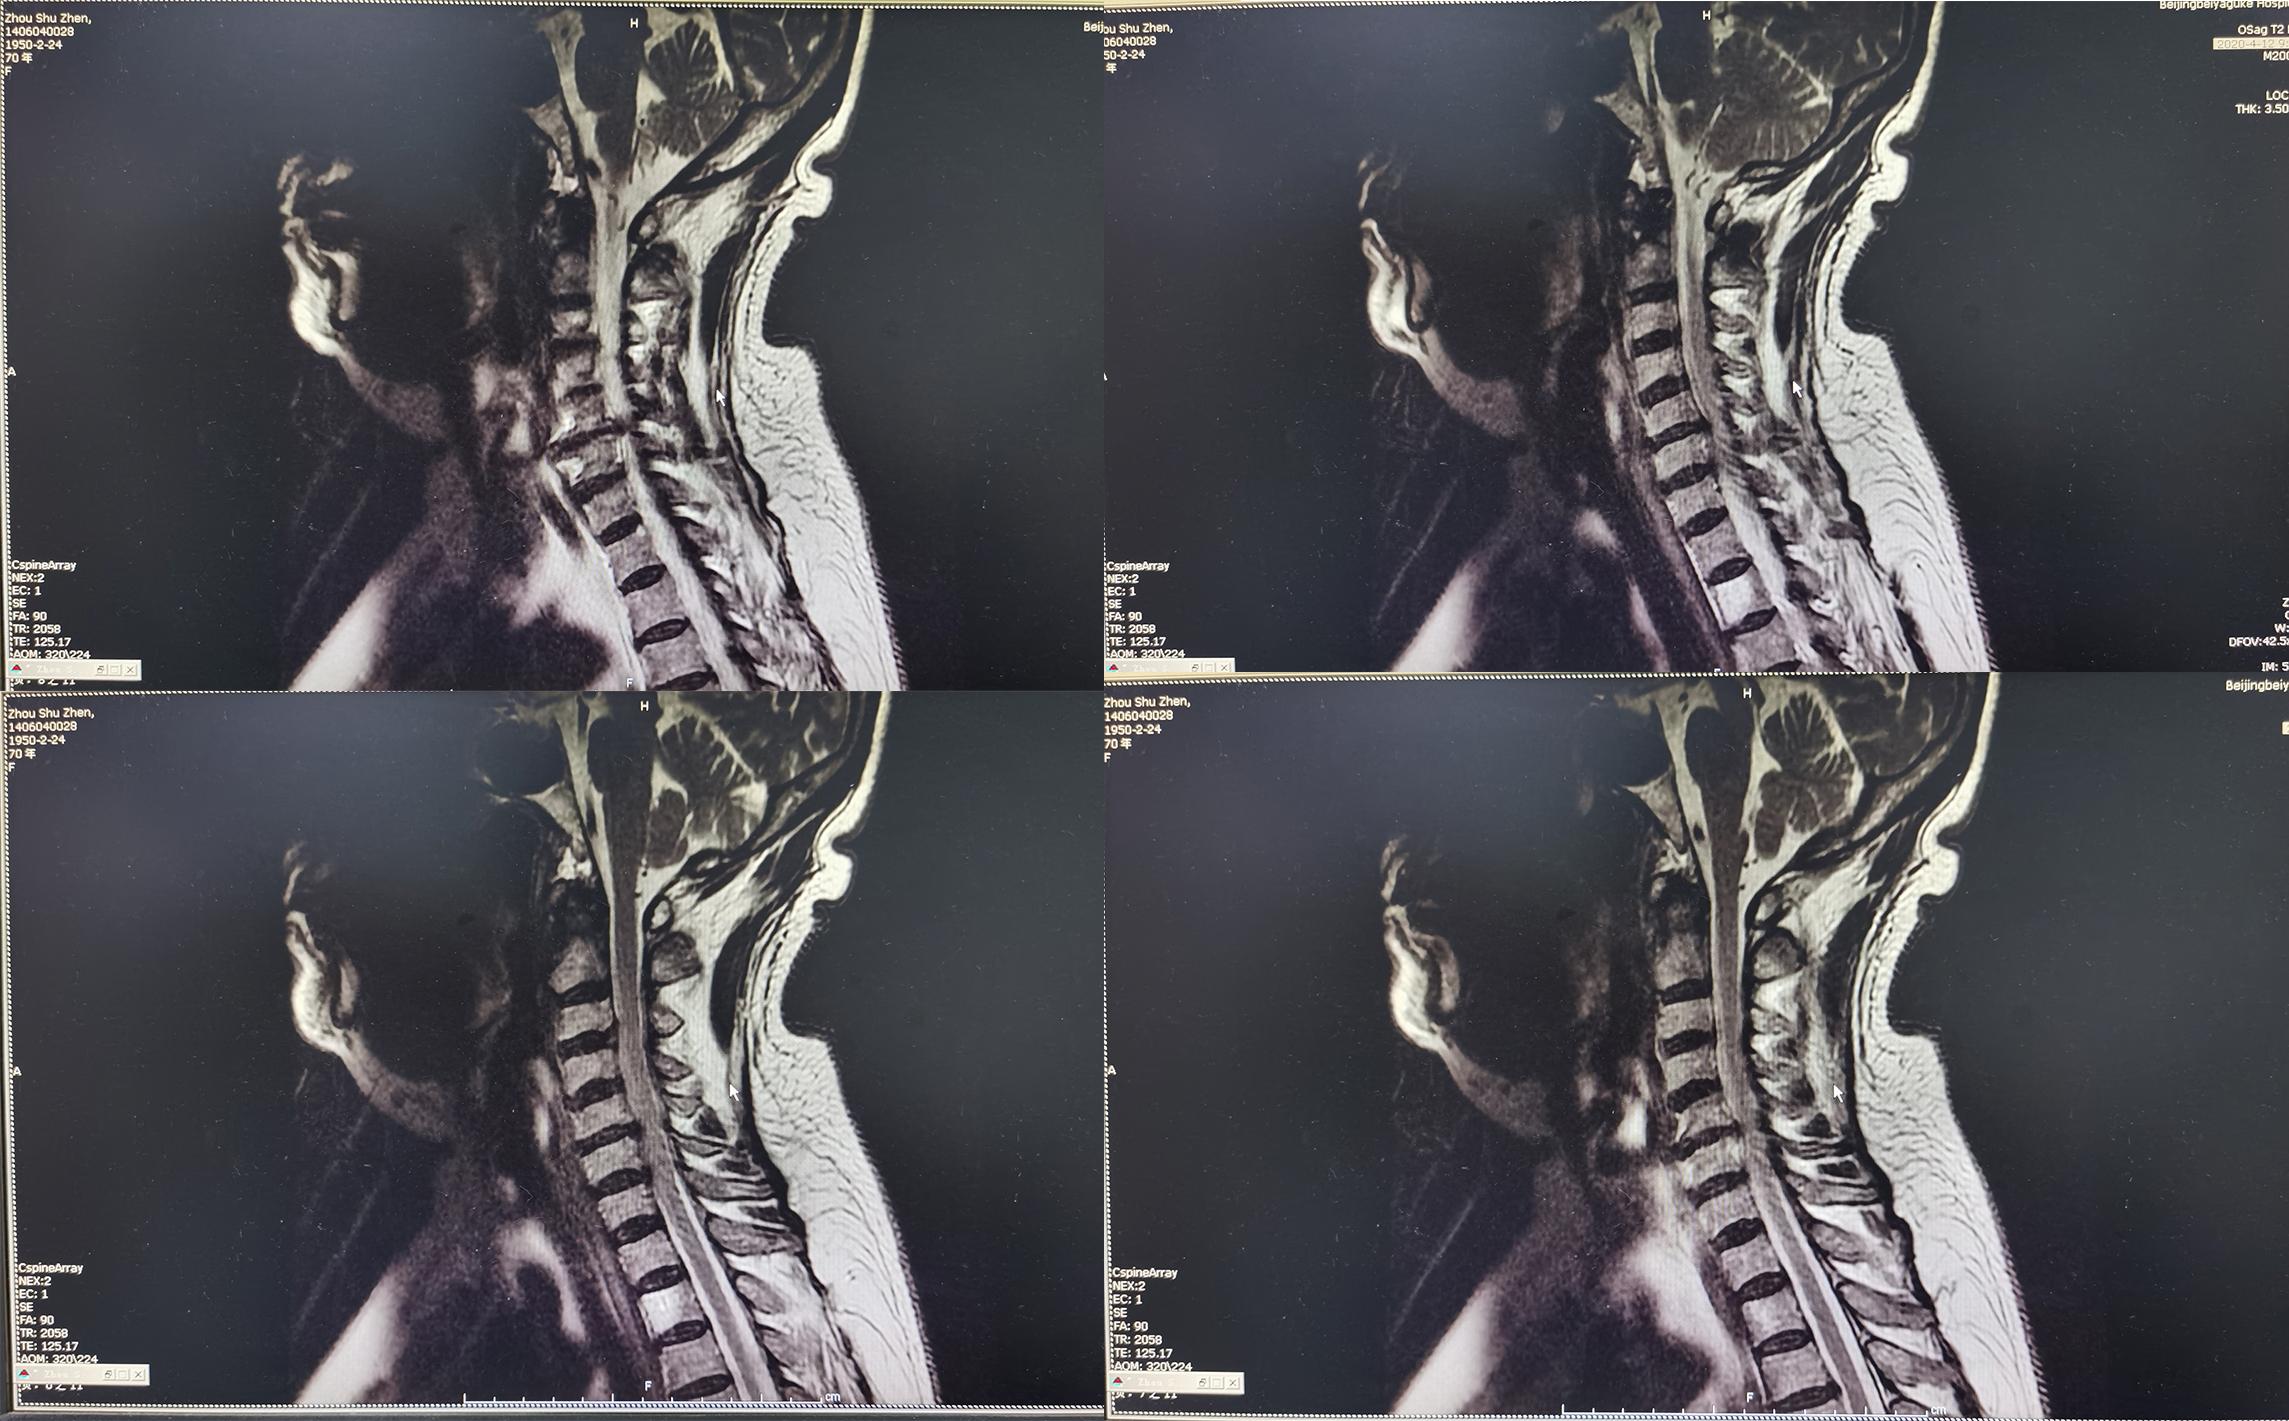

入院后第二天2020年4月12日查颈椎MR示颈椎病(脊髓型)( 图-2 )。

图-2: 2020年4月12日颈椎MR